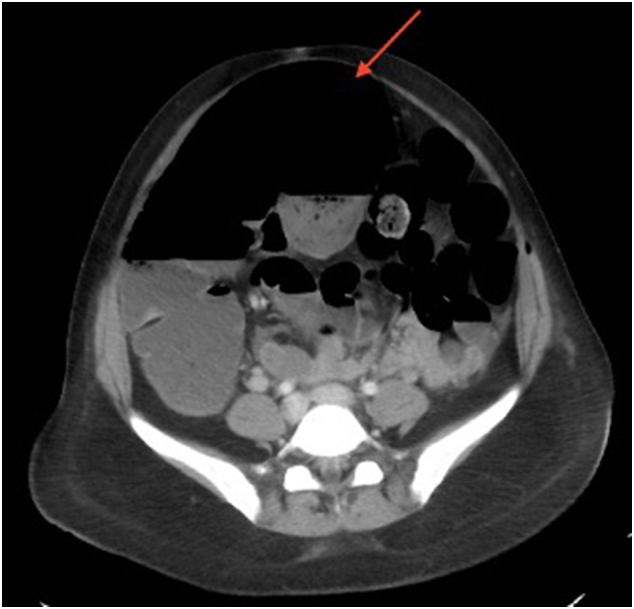

Twelve hours after her operation the patient became nauseated, her abdomen became distended, and she reported severe generalized abdominal pain. An abdominal radiograph was obtained which demonstrated air fluid levels concerning for an obstruction or ileus (Fig. 1). She was made nil per os, started on intravenous hydration, and a general surgery consultation was placed. Upon examination the patient had a distended abdomen with generalized tenderness to palpation as well as rebound and guarding. Her vital signs were within normal limits. Laboratory evaluation revealed a leukocytosis to 18,200 k/μL, a lactic acidosis to 3.6 mmol/L, and a hemoglobin of 9.4 g/dL. A nasogastric tube was placed with immediate return of 800 cc of bilious fluid and an urgent computerized tomography (CT) of the abdomen and pelvis was performed. The CT scan demonstrated decompressed small bowel with cecal dilation up to 10.4 cm and superior displacement of the cecum without pneumatosis, concerning for a cecal bascule (Fig. 2). Given the patient's worsening symptoms and concerning CT scan findings, she was taken to the operating room, roughly 16 h after her index operation, for urgent abdominal exploration.

Fig. 2.

Computerized tomorgraphy (CT) scan of the abdomen and pelvis showing cecal dilation and superior displacement of the cecum (red arrow), concerning for cecal bascule.